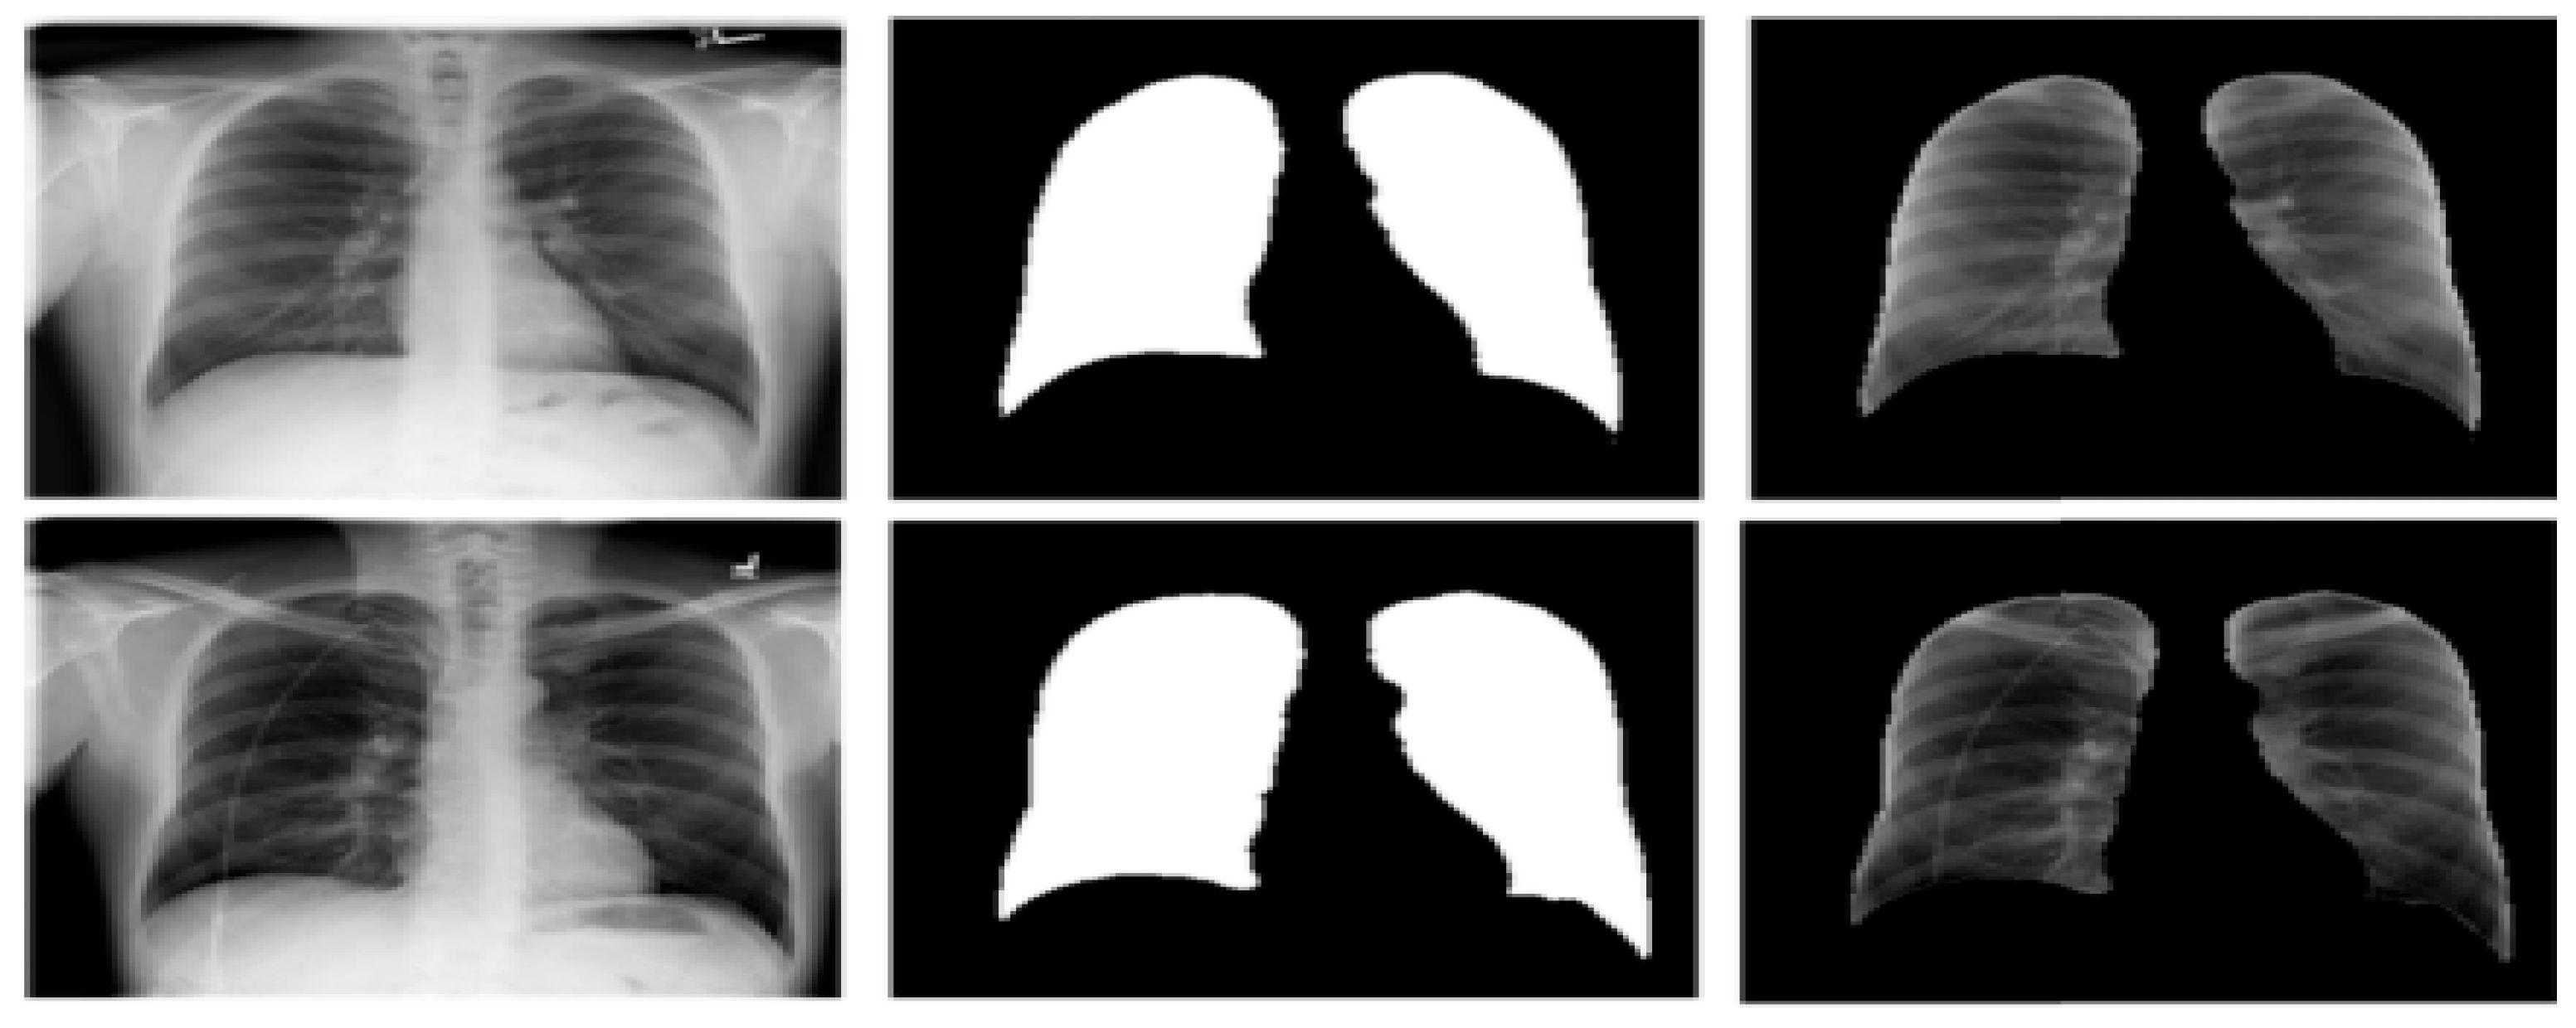

3.3. Lung Segmentation